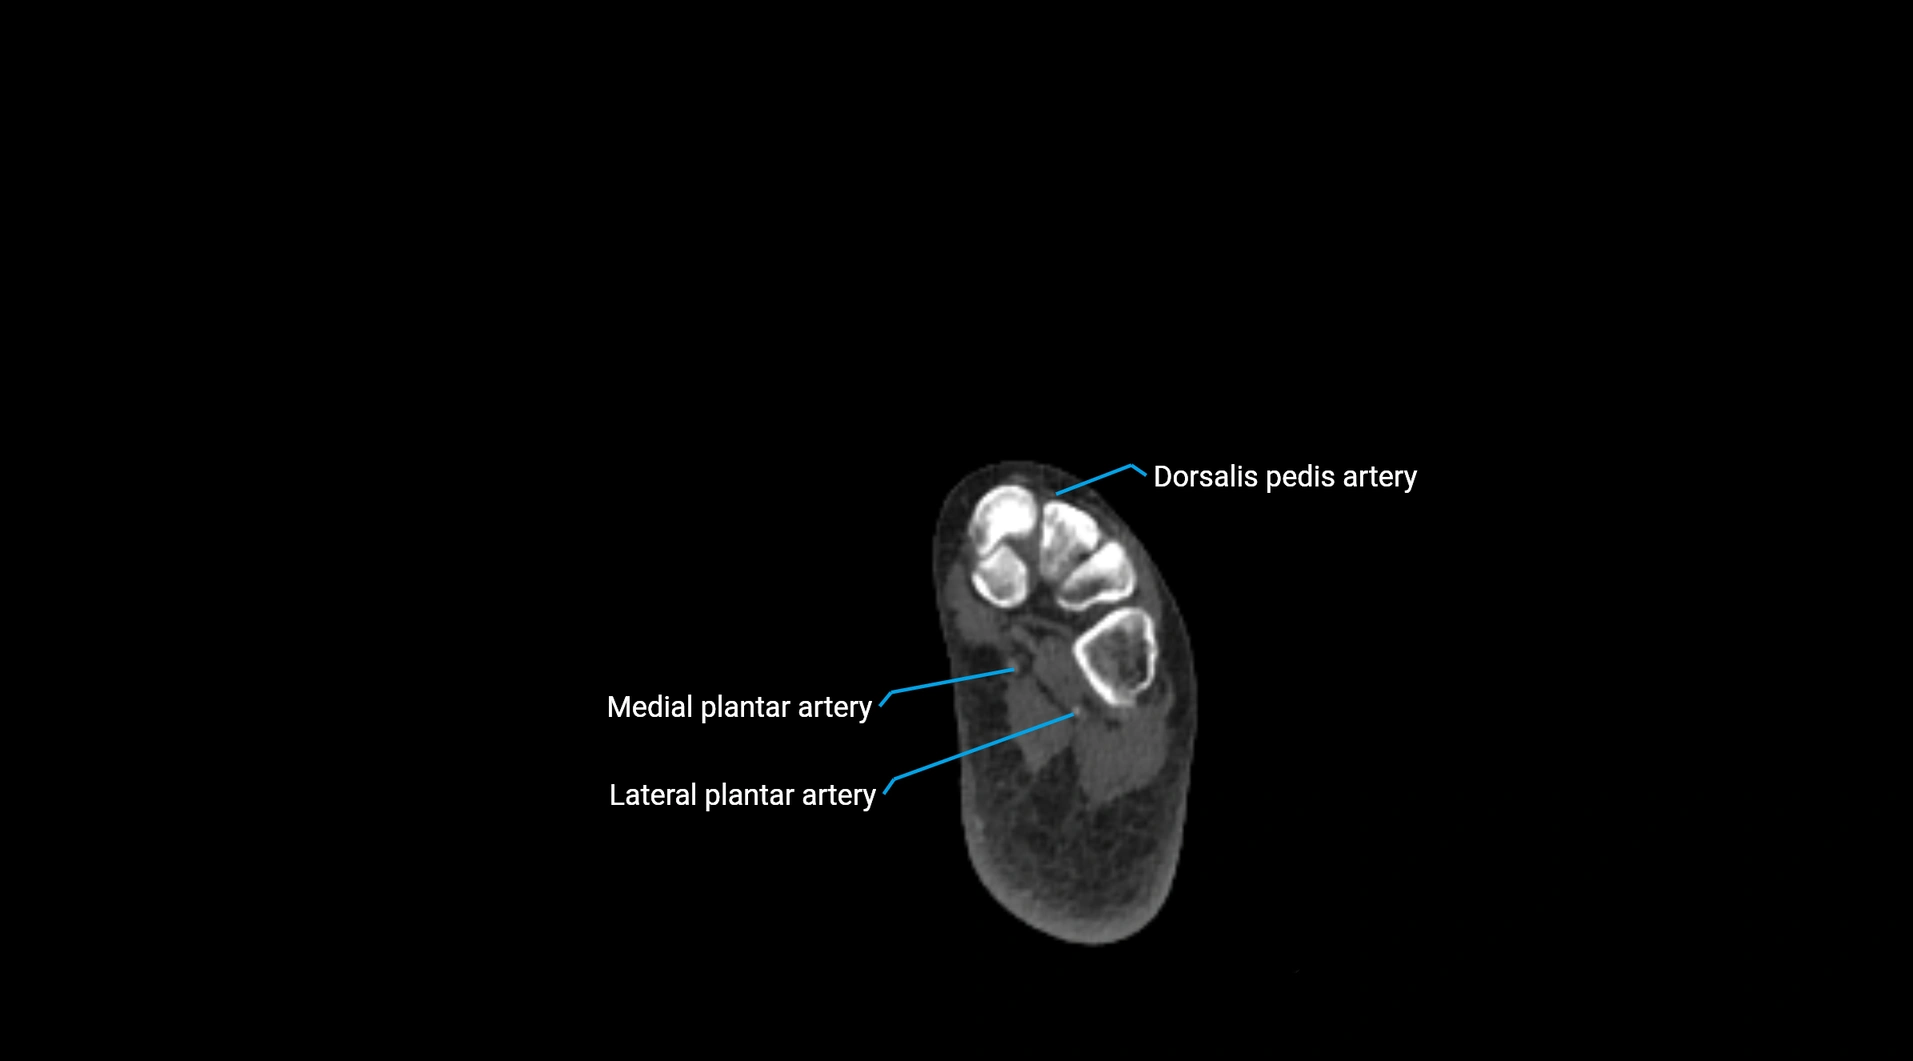

Contrast-enhanced CT (CTA):

• Gold standard for abdominal aortic imaging

• Provides excellent detail of lumen, wall, aneurysm, thrombus, and branch vessels

• Multiplanar and 3D reconstructions help in aneurysm measurement, stent graft planning, and dissection evaluation

• Detects acute rupture, traumatic injury, or occlusion with high sensitivity